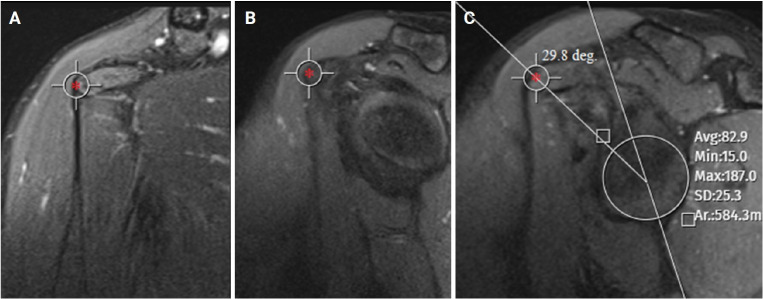

Methods: This study included 72 patients who underwent surgery for ASI and 72 age- and sex-matched controls. The sagittal central glenoid- coracoid angle (scGCA) and axial central glenoid-coracoid angle (acGCA), which assess the coracoid apex position relative to the glenoid center, the glenoid version (GV), and glenoid inclination (GI) were evaluated using magnetic resonance imaging. The critical shoulder angle (CSA) was measured using true anterior-posterior radiographs.

Abstract Image